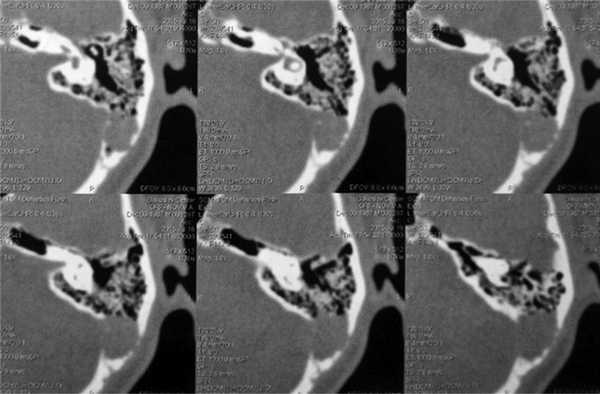

На компьютерной томограмме височных костей отмечается хорошая пневматизация барабанной полости, антрума и образование мягкотканной консистенции размером 3×4 см с деструкцией клеток в задних отделах сосцевидного отростка и разрушением стенки сигмовидного синуса слева (рис. 2).

Рис. 2. КТ височных костей. Аксиальная проекция. Отмечается хорошая пневматизация барабанной полости, антрума и образование мягкотканной консистенции размером 3×4 см с деструкцией клеток в задних отделах сосцевидного отростка и разрушением стенки сигмовидного синуса слева.